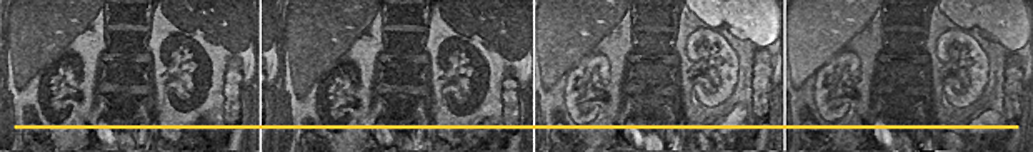

Figura 16-03:

Four images taken out of a dynamic study of the kidneys. During the examination, both kidneys move in all three dimensions and rotate. In this example, the right kidney moves several pixels up and down during the time series (yellow line). Mathematical processing of the images can help eli­mi­na­te some of the movement and facilitate processing the time series.